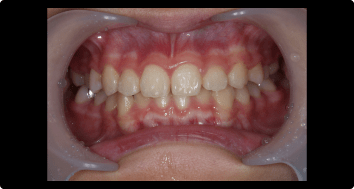

症例1:受け口の矯正治療

BEFORE

AFTER

症例概要

年代・性別

10歳代 女性

主訴

上下反対の噛み合わせが気になる

治療内容

ムーシールドを用いた矯正治療

治療期間

4ヶ月

治療のリスク

装置の装着時間を守らないと、治療結果が伴わない場合があります

治療費用

440,000円(税込)